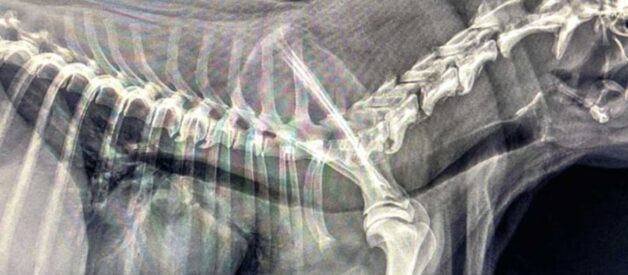

Zapadanie tchawicy u psów (TCS-Tracheal Collapse Syndrome) jest przewlekłą chorobą układu oddechowego obserwowaną głównie u raz małych i miniaturowych (Yorkshire terrier, Szpic miniaturowy, Chihuahua). Choroba ta polega na „zapaści” tchawicy co w znacznym stopniu ogranicza jej drożność. Odnotowuje się dwa procesy przyczyniające się do rozwoju tej choroby. Pierwszy z nich, najbardziej klasyczny, to dynamiczna obstrukcja dróg oddechowych, spowodowana chondromalacją i osłabieniem mięśni tchawiczych. Drugi proces, to statyczna obstrukcja związana z malformacją chrząstek tchawiczych i ich układem przypominającym literę „W”.